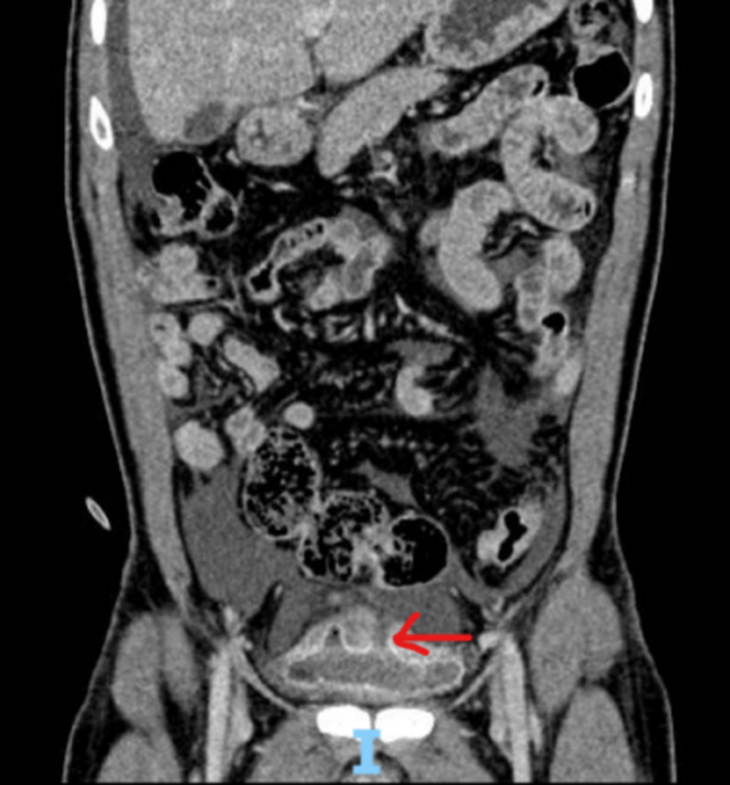

Tomografia computadorizada abdominal e raio-X da bexiga mostraram líquido livre no peritônio e ruptura da bexiga na cúpula vesical - Foto: Fornecida pelo hospital

Cerca de 4 horas depois, o paciente foi levado ao hospital pela família. Através de exame clínico e radiografia, foi constatada ruptura intraperitoneal da bexiga com lesão hepática grau I.